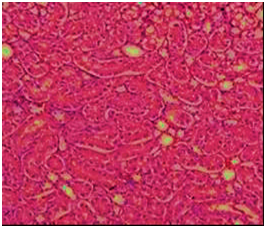

The histopathological study

The biochemical results were confirmed by the histological examination in liver and kidney tissues. The histological examination of the structure of liver in the control group was normal hepatocytes and central (Figure 3). Liver of rats in group four that fed AFB1-contaminant diet (2.5 mg/kg feed) alone showed enlarged portal area and dilated thick wall portal vein and also appeared accumulation of cellular infiltration and fibrous tissues around proliferated bile ducts thick (arrow) (Figure 4). Rats fed on AFB1 free diet and treated with ozone showed the hepatic cells and central vein are nearly normal (Figure 5). In the other hand, animal in group fed AFB1-contaminated diet after ozonation at 20 and/or40 ppm ozone gas showed the area around the central vein is nearly normal and nearly normal hepatocytes and the damaged area around the portal tracts is not noticed (Figure 6). The liver is the main target organ for AFs and chronic exposure to low levels in foodstuffs cause liver fibrosis and primary liver cancer.29 Microscopic examination of kidney section of control rats showed the normal structure of renal tissue in convoluted tubules and the Bowman capsule (Figure 7). But rats fed AFB1-contaminant diet alon showed distal tubules have fatty degeneration and eosinophilic cytoplasm as well as pyknotic nuclei. Interstatial edema and inflammation also present (Figure 8). While rats fed on AFB1 free diet and treated with ozone showed the nearly normal structural of renal tissue and normal convoluted tubules and the Bowman capsule also rats fed AFB1-contaminated diet after ozonation (Figure 9 & Figure 10). In the current study, animals’ fedAFB1 free diet after ozonation (ozone gas treated wheat alone) did not show any significant effects however, when the AFB1-contaminated wheat grain after ozonation, a significant improvement was observed in the serum biochemical parameters tested and histological examination in liver and kidney tissues. This could be due to the AFB1 been degraded after ozone treatment of the contaminated wheat. These results were in agreement with.22 The primary reaction site of ozone in AFB1 and is the C8-C9 double bond at the terminal furan. This site has been associated with AFB1 toxicity, mutagenicity, and carcinogenic.5 This reaction resulted in the formation of aflatoxinmolozonide which is further change to aflatoxinozonide. This compound is unstable and change to aldehydes, Ketones, acids and CO2 (Figure 11). Ozone is a decomposes to form oxygen gas and therefore can be classified as a no persistent chemical; however, it must be generated at the location of its intended use

Figure 8 Section in kidney of of rat fed AFB1-contaminated diet showing some distal tubules have fatty degeneration and eosinophilic cytoplasm as well as pyknotic nuclei (arrow) or hyaline casts (circle). Interstitial edema and inflammation also present (H&E 200).

Figure 9 Section in kidney of group fed on AFB1 free diet and treated with ozone gas showing nearly normal convoluted tubules and the Bowman corpuscle   (H &E 200).